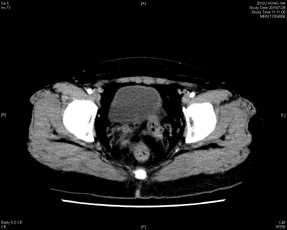

2018-05-08外院 胸部CT提示,两肺多发小结节,考虑转移瘤可能,左肺下叶肺大泡,右肾小结石。2018-5-10外院 全腹CT平扫增强示:直肠中下段肠壁不规则增厚,考虑恶性肿瘤,伴外膜浸润,周围淋巴结显示,左侧盆腔淋巴结肿大。结肠镜示:直肠溃疡性肿块。